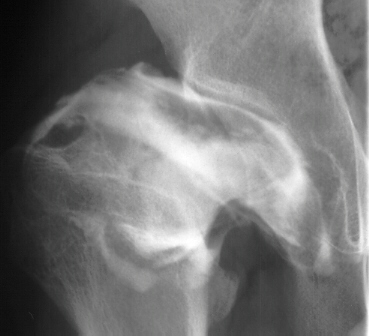

- 2 month Office Follow Up: Rt hip Xray: progressive destruction of capital

femoral epiphysis, cystic changes in metaphysis consistent with AVN.

- Age 6: Valgus osteotomy for subluxation and 2cm leg length inequality.

- Age 15: Valgus osteotomy for hip incongruity.

- Age 20: Hip arthroscopy. Hip fusion recommended.

This case is an example of untreated septic arthritis which caused avascular

necrosis of the proximal femur. The primary cause of this is undrained

septic hip. Repeated aspiration is not adequect treatment of a septic hip.